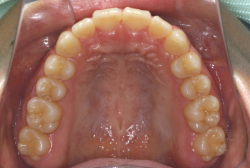

混合歯列期から治療開始した側方拡大による非抜歯症例

「配列の凸凹を治したい」という主訴で来院したケースです。診断の結果、永久歯がすべて生えそろうと、かなり厳しい叢生(歯並びの凸凹のことです)になる可能性が高いと判明しました。原因としては特に上の顎の骨が小さいため、歯を収容する容量不足になっていると診断しました。このケースの場合は、成長発育期に治療開始しますので、顎の骨を土台ごと大きくすることが可能です。

そこで、まず急速拡大装置を使用して上顎骨の拡大を行い、上顎骨の容量が拡大したことを確認後、マルチブラケット装置を使って全体の修正をする、と言う二段階の作戦をとることになりました。

この時期に使う急速拡大装置は、適切な診断に基づいて正しく使用することで確実に骨を大きくすることができます。拡大することで隙間が確保できるので、永久歯の抜歯を避けることができます。

急速拡大装置を1日1回装置の中央にある拡大ネジを、ご自身で回して頂くことで25日間くらいかけて、6mmほど拡大しました。拡大後は、上顎の前歯の隙間が広がっていることがお分かりいただけると思うのですが、土台の骨ごと広がるのでこのような隙間ができます。その後1年半くらいマルチブラケット装置を使用して、全体の修正を行いました。

結局、歯の本数を減らすことなく、すべてご自分の歯を残して正しい配列にすることができました。このケースの場合、2009年10月より拡大と経過観察を行い、2012年3月より1年2ヶ月マルチブラケット装置を装着、2013年5月に治療を終了しました。2段階で行う治療としては短期間で終了しているケースと思います。